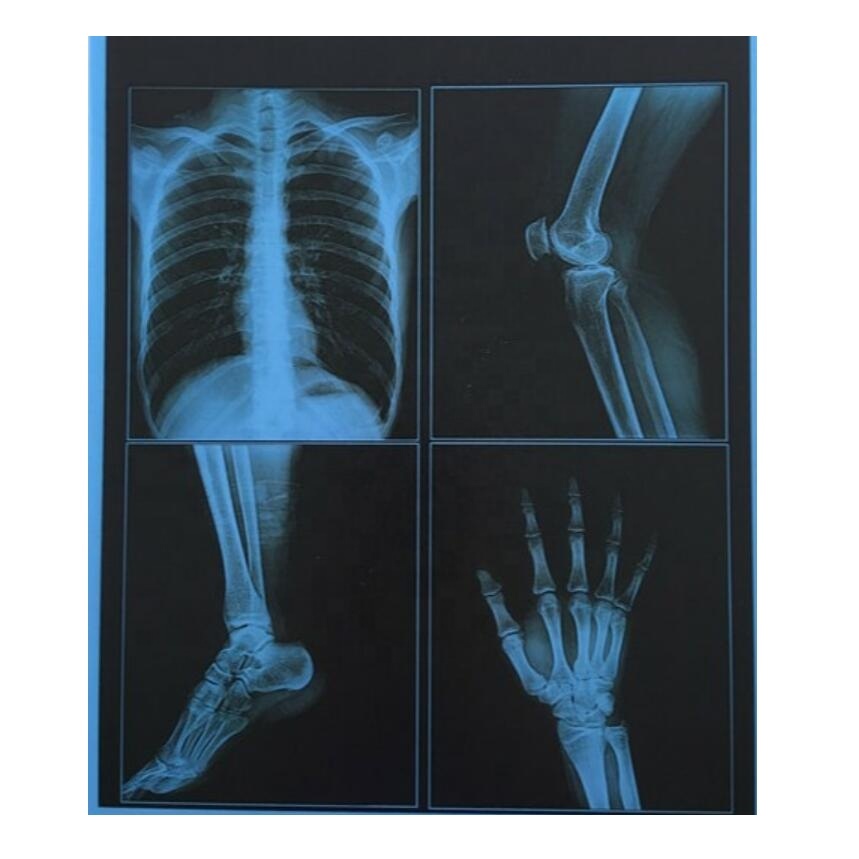

Рентгеновские технологии: усиленные экраны 35x35